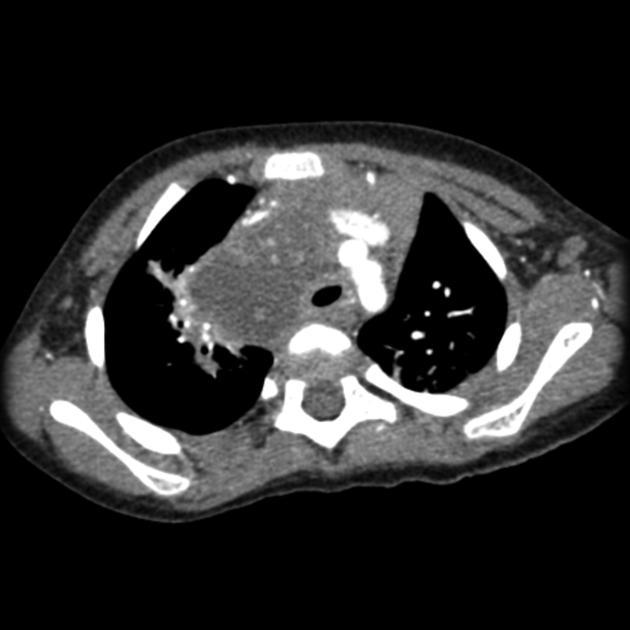

В нативном режиме определяется объемное образование в переднем или верхнем средостении с однородной или неоднородной плотностью, что соответствует увеличенным лимфатическим узлам, сдавливающим окружающие структуры.

В режиме сканирования мягких тканей визуализируется конгломерат лимфоузлов с нечеткими контурами, изменение конфигурации трахеи и крупных сосудов, возможное их смещение или компрессия.

В режиме оценки сосудистого русла средостения визуализируется компрессия верхней полой вены, деформация дуги аорты или легочной артерии, что указывает на распространённость процесса.